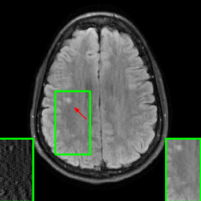

Figure 10 presents visual comparison of image reconstructions and their associated reconstruction errors within a closely examined region. Each image in the figure includes two inset panels in the bottom-left and bottom-right corners. The bottom-left inset panel, enclosed within a green bounding box, serves as a reference for the region of interest in the image. In contrast, the bottom-right inset panel depicts an error map in relation to the ground truth. Notably, our method stands out in its ability to capture more features from the original image, surpassing the performance of alternative methods (as also evident from the reported PSNR values).